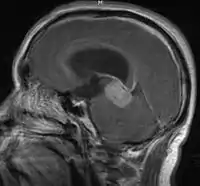

- Mainly located in midline structures, suprasellar region or pineal gland, also basal ganglia and hypothalamus

- Pineal Gland Germinoma

- Suprasellar Germinoma

- Toronto; 2006 (1995-2004) PMID 16530340 -- "Limited-field radiation for bifocal germinoma." (Lafay-Cousin L, Int J Radiat Oncol Biol Phys. 2006 Jun 1;65(2):486-92.)

- Retrospective. 6 patients with bifocal germinoma (pineal + suprasellar). All with diabetes insipidus at presentation. Treated with chemo followed by limited-field RT (whole ventricle 24-40 Gy +/- boost). Median F/U 4 years

- Conclusion: Bifocal germinoma can be considered locoregional rather than metastatic disease